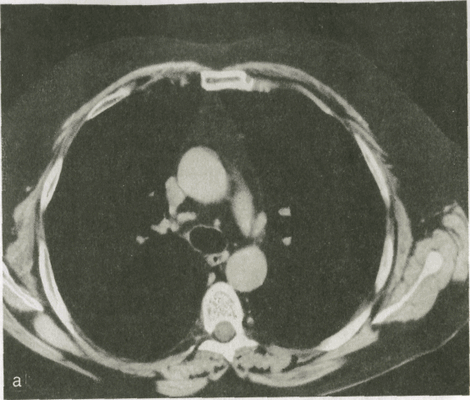

Более ценные сведения о морфологии органов грудной полости позволяет получить компьютерная томография. В зависимости от цели исследования врач выбирает «ширину окна» при анализе изображения. Тем самым он делает упор на изучение структуры либо легких, либо органов средостения.

В нормальных условиях плотность легочной ткани, по данным денсито-метрии, колеблется от —650 до -850 Н. Такая низкая плотность объясняется тем, что 92 % легочной паренхимы составляет воздух и лишь 8 % — мягкие ткани и кровь в капиллярах. На компьютерных томограммах определяются тени легочных артерий и вен, четко дифференцируются главные, долевые и сегментарные бронхи, а также межсегментарные и междолевые перегородки.

Рис. 5. Компьютерные томограммы легких одного и того же пациента, выполненные при разных технических условиях.

а - для исследования органов средостения; б - для исследования легочной ткани.

Фоном для медиастинальных органов является жировая клетчатка средостения. Ее плотность колеблется от -70 до —120 HU. В ней могут быть заметны лимфатические узлы. В норме они круглой, овальной или треугольной формы. Если величина узла превышает 1 см, то его считают патологически измененным. С помощью срезов на разной глубине получают отображение пре- и паратрахеальных лимфатических узлов, узлов в аортопульмональном «окне», в корнях легких и под бифуркацией трахеи. КТ играет важную роль в оценке состояния органов средостения: она позволяет изучить тонкие детали морфологии легочной ткани (оценка состояния долек и перидольковой ткани, выявление бронхоэктазий, участков бронхиолярной эмфиземы, мелких очагов воспаления и опухолевых узелков). КТ часто необходима для установления отношения обнаруженного в легком образования к пристеночной плевре, перикарду, ребрам, крупным кровеносным сосудам.